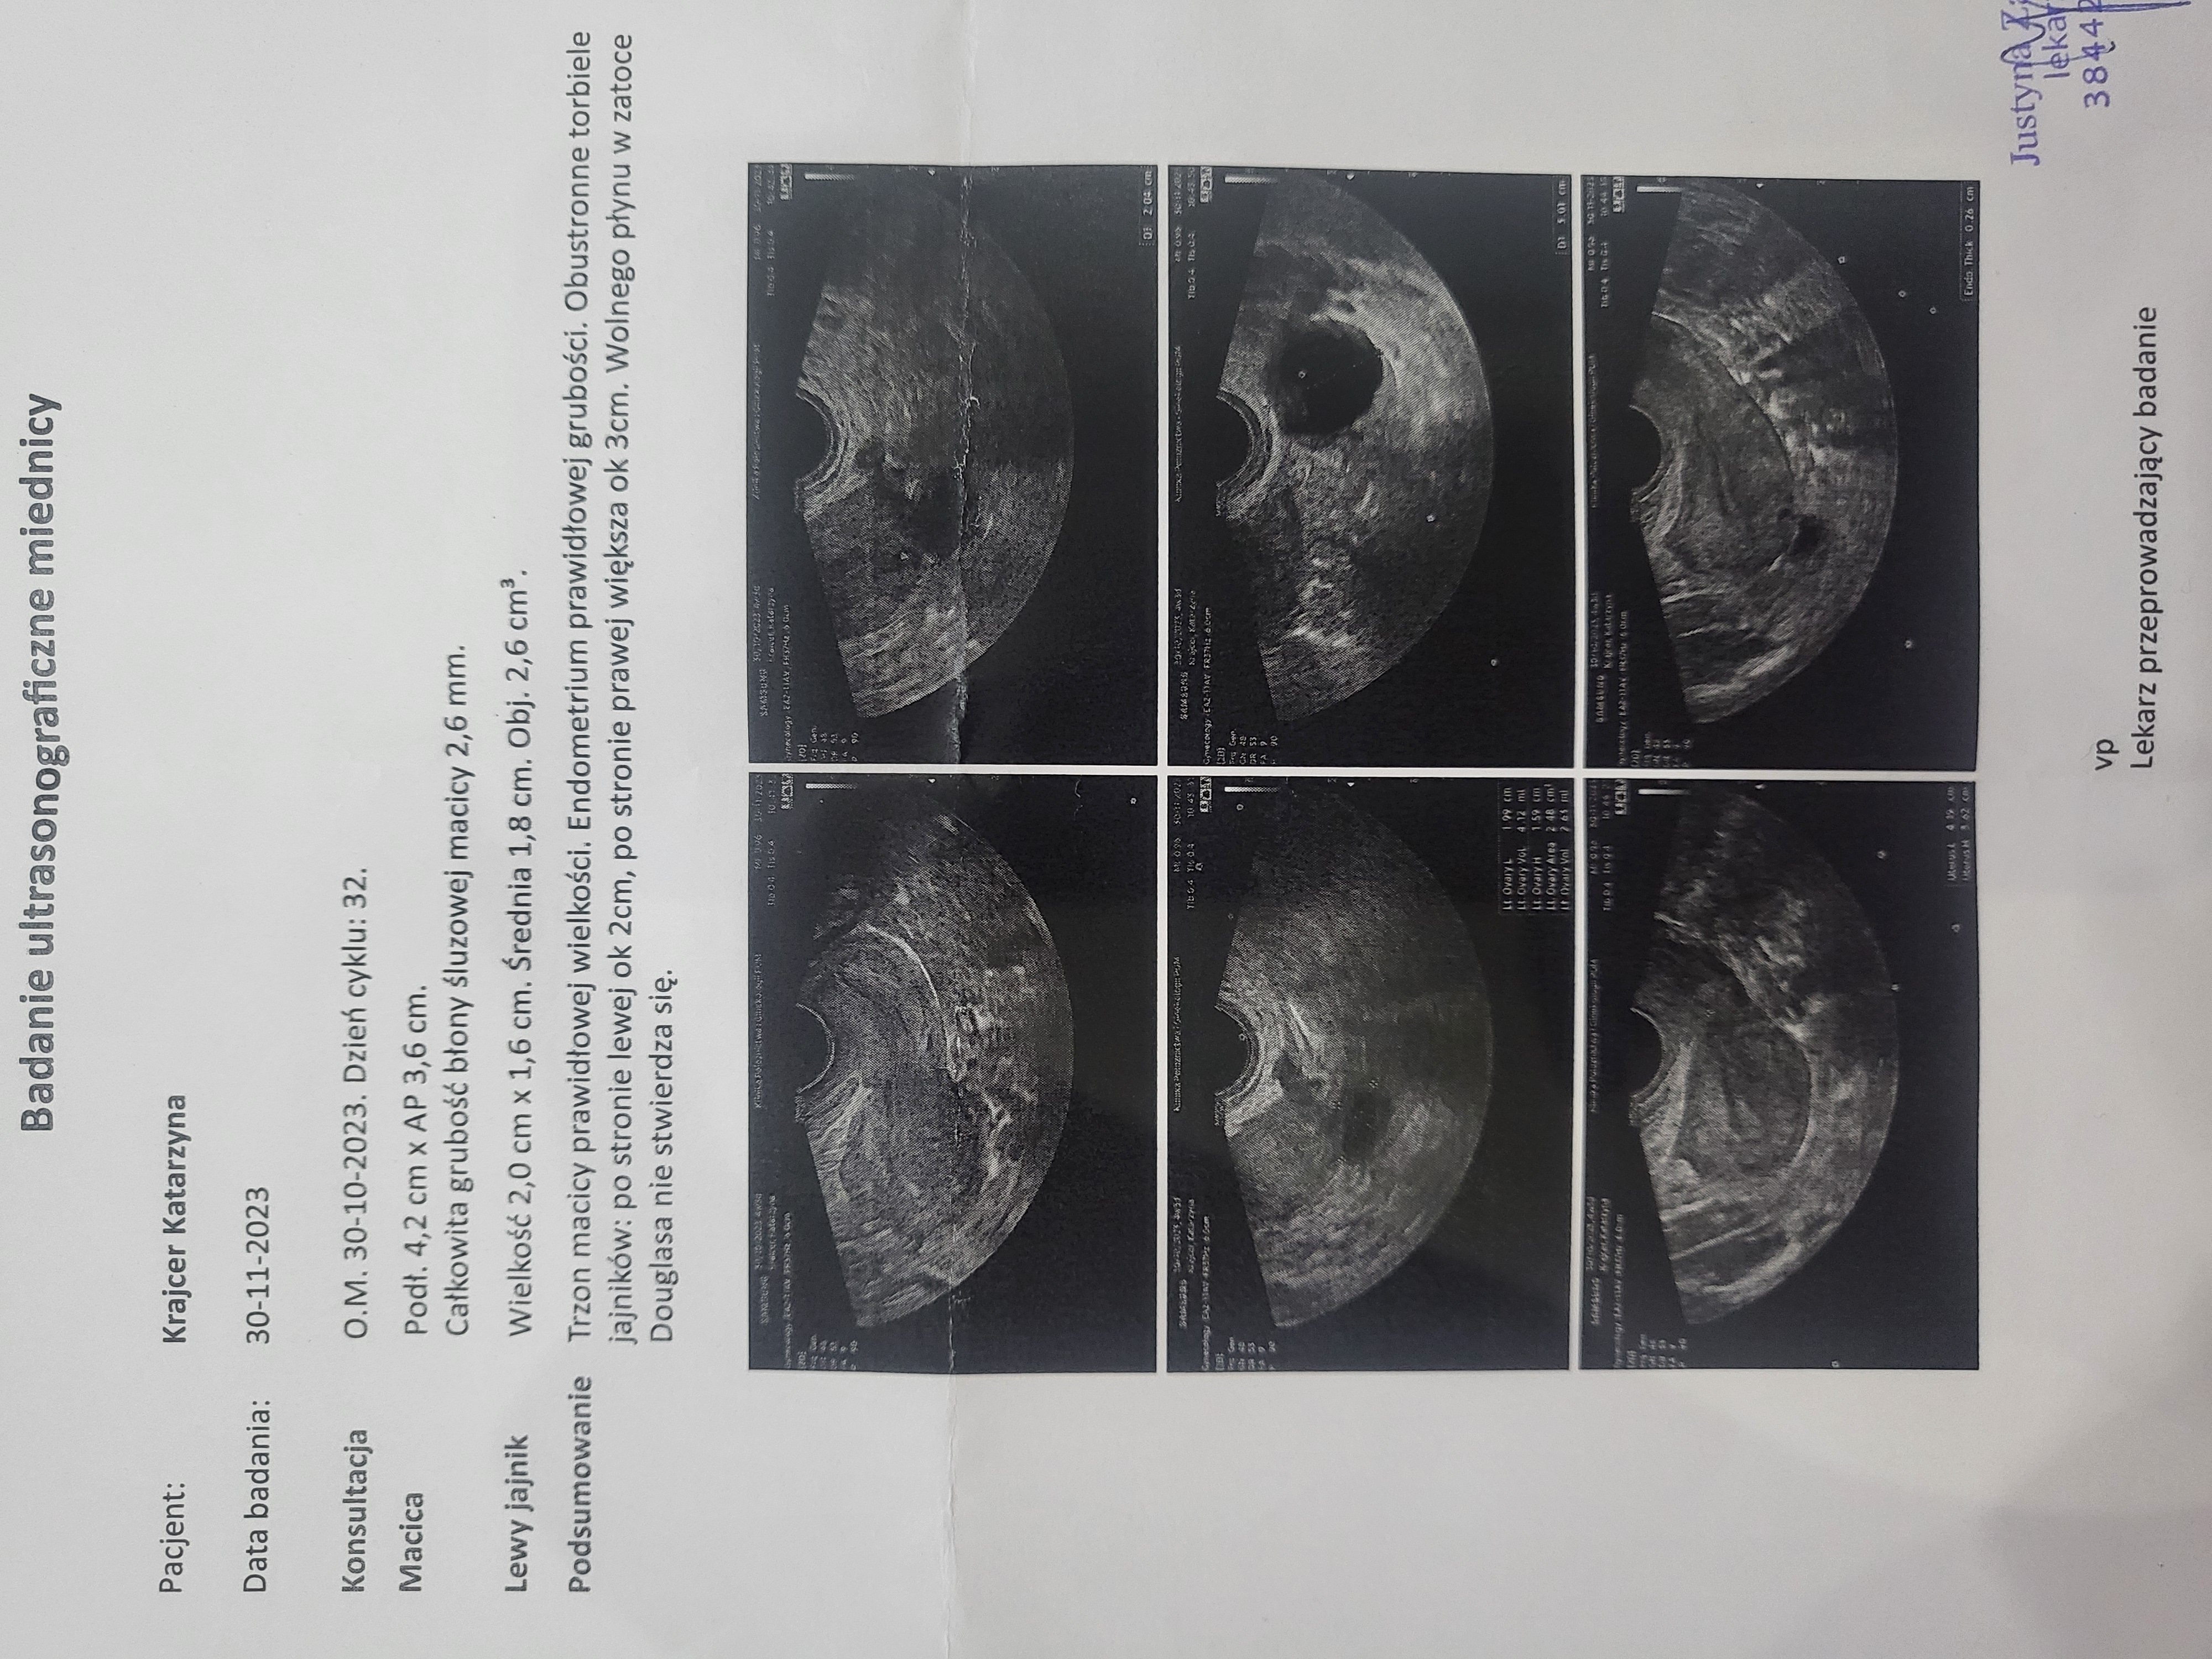

Dr Mikołaj Karmowski – ginekolog specjalista w dziedzinie leczenia endometriozy, postawił diagnozę endometrioza i adenomioza.

Pani doktor przy każdym USG transwaginalnym odnajdywała torbiele: mniejsze, większe, mnogie, dwukomorowe – lecz były ,, do obserwacji”. Pomimo przyjmowania tabletek hormonalnych one nadal się pojawiały. W celu diagnozy skierowano mnie na laparoskopię, która się nie odbyła ze względu na planowaną w niedługim czasie operację usunięcia dwóch przepuklin pachwinowych.

Postanowiłam umówić się na wizytę, która miała miejsce 04.03.2024r.

Dr Karmowski prosił, abym usiadła na fotelu i po dokładnym przeprowadzeniu badania opowiedział o wszystkim co mi dolegało. W końcu na swojej drodze spotkałam lekarza, który chce i potrafi mi pomóc.